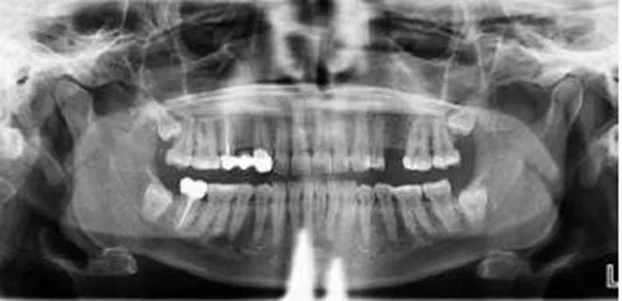

Cloudy artifact down the center of the radiograph

This artifact most commonly looks like a cloudy fuzz down the center of the panoramic radiograph.

This is typically caused when the patient’s spine is “hunched”, or sometimes referred to as “goosenecked” vs. being erect or, even better, stretched.

If the spine is hunched, it means the x-ray must travel through more bone before it reaches the anterior teeth which can result in much less energy to exposing this region of the anatomy. This can result in the cloudiness seen down the center of the radiograph.

The most effective technique to remove this artifact is to have the patient hold the grab bars on the unit and move their feet forward so that the patient is in a “leaning back” position. While this is the ideal approach, we also have seen that this can be easier said than done with some patients (e.g. an elderly patient that cannot hold themselves in this position, and may have an inherent hunch in their spine). Therefore, even if the patient cannot be positioned in this leaning back manner, simply helping the patient to stand as erect as possible will help reduce this anterior artifact.